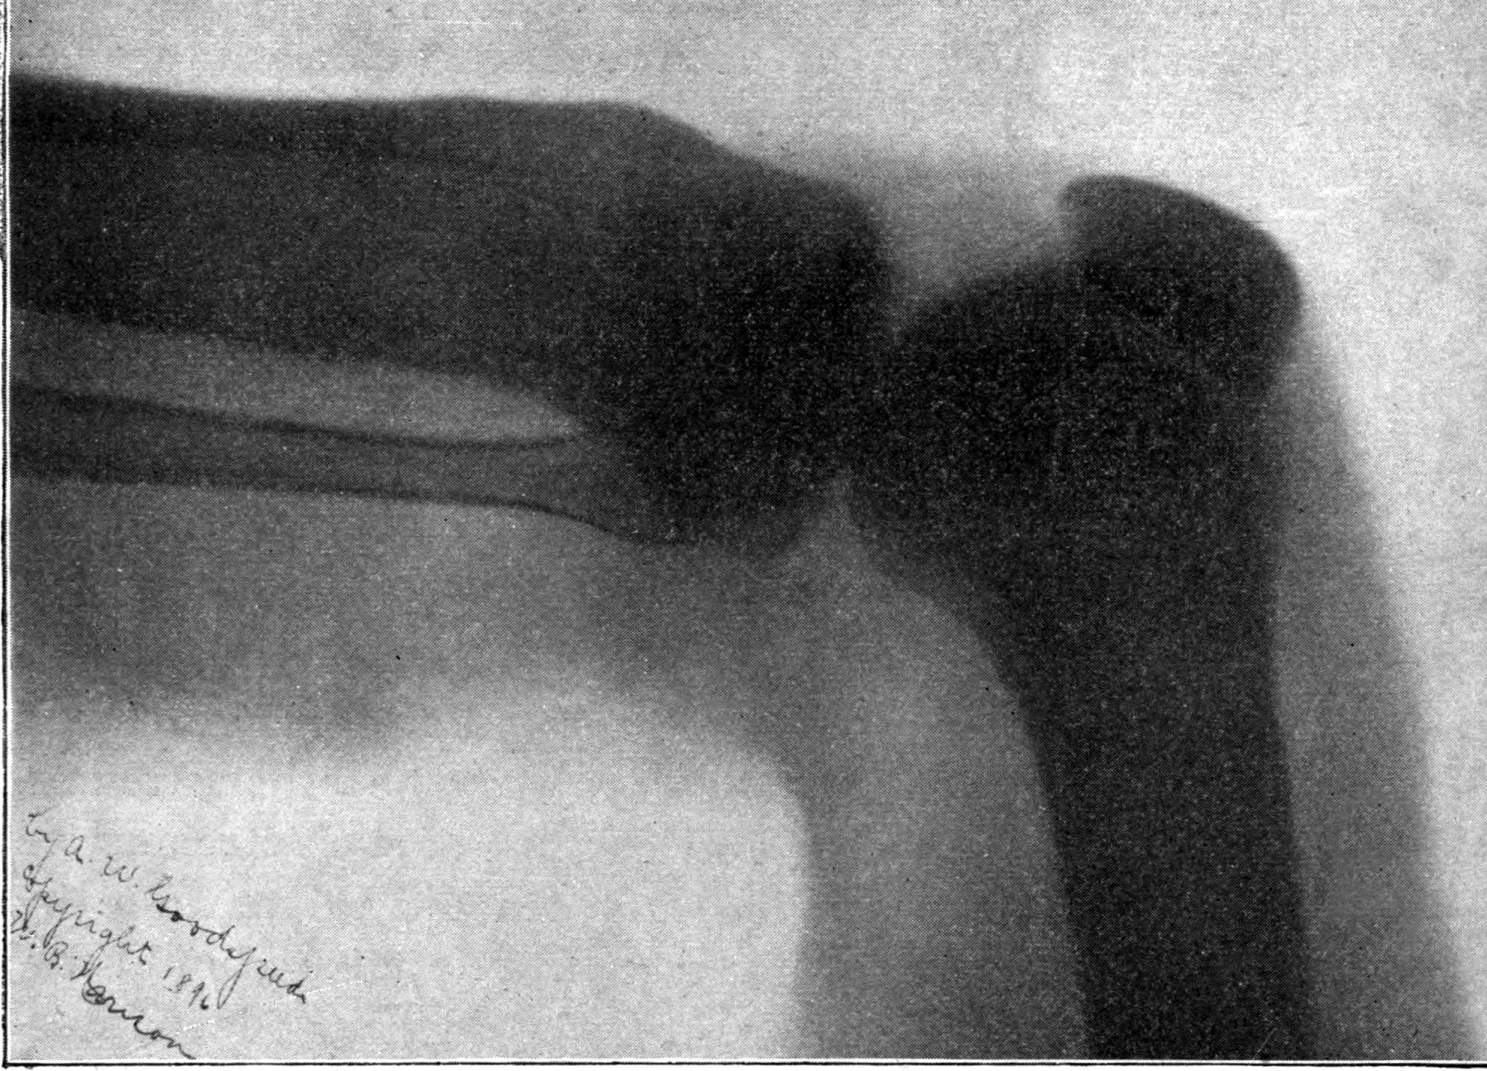

Fig. 1.—Head.

Fig. 2.—Broken Arm, Overlapping.

(Due to defective setting.)

Fig. 3.—Ribs.

Fig. 4.—Knee, Knickerbocker Buttons, Bullet in Femur.

FROM SCIAGRAPHS BY PROF. DAYTON C. MILLER. § 204.